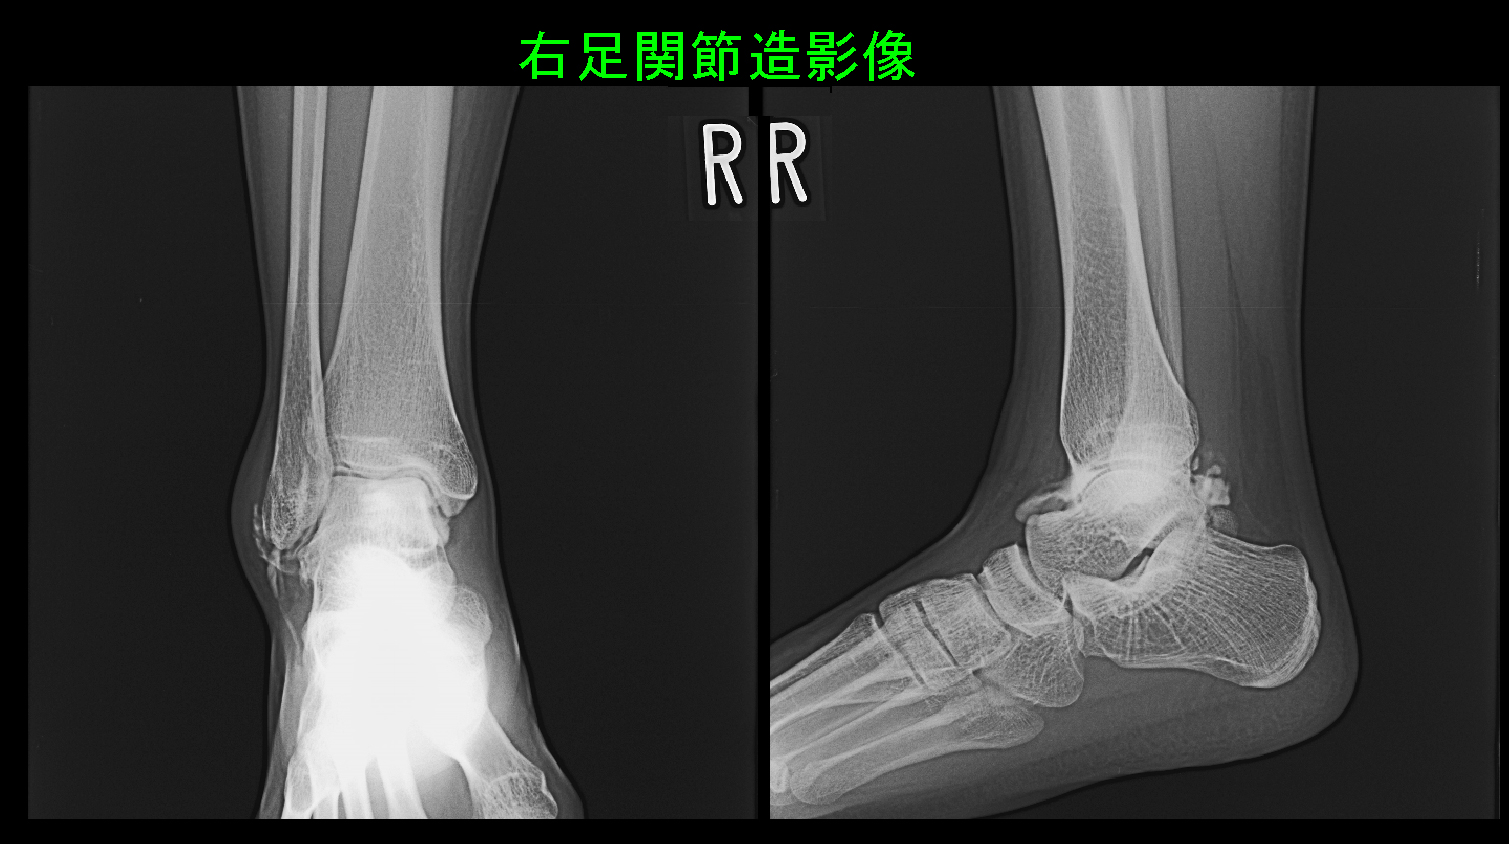

17才の高校3年のサッカー選手です。平成24年5月11日大会中に右足関節を捻挫し、プレーできなくなり交代し、同日歩行困難で(土曜の午後であったので)当院を受診されました。明日県北大会の準決勝があるけれど、明日か明後日の3位決定戦に勝てば県大会に出場できるということでした。この症例はここで提示した症例3人の中で最も古い時期のものとなりますが、当時からMRI検査で骨損傷がない症例にはスポーツへの早期復帰に向けて関節内注入療法を行っていました。私は明日の大会に出場可能かどうかは分からないけれど、とりあえず検査してみて、関節内注入療法の実施も考慮することを提案しています。

17才男サッカー MR1.jpg

右足関節は骨損傷はなく、GR矢状断の所見で軽度の関節炎の所見です。

17才男サッカー MR2.jpg

GR水平断の所見では右足関節は赤矢印の部分で前距腓靭帯が白くなり断裂しています。左足関節では黒く連続性がしっかり確認できます。しかし、GR水平断の別の画像では前距腓靭帯が連続している画像も確認され、骨の損傷は確認されず前距腓靭帯の部分断裂と診断されました。関節内注入を行い、安静保持のために中学の女子選手と同じ簡易シーネを1~2日装着することを勧めました。投薬は大会期間中の4日分行っています。シーネを外して膝の屈伸が可能となればプレーしても良いのではと説明しています。この患者さんは1日のみの受診でしたが、12日後の5月23日に電話で経過を聞きました。翌日の準決勝は欠場したけれど、3位決定戦にはフル出場して2ゴール決め県大会に出場できることになったと、うれしそうに報告してくれました。